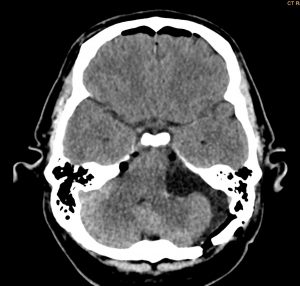

Ασθενής άνδρας, 52 ετών με κώφωση αριστερά και ιλιγγική συνδρομή.

Η μαγνητική τομογραφία εγκεφάλου ανέδειξε χωροκατακτητική εξεργασία στην αριστερή γεφυροπαρεγκεφαλιδική γωνία συμβατή με ακουστικό νευρίνωμα (αιθουσαίο σβάννωμα) και πίεση επί του στελέχους (Koos IV).

Ο ασθενής υπεβλήθη σε αριστερή οπισθοσιγμοειδική κρανιοτομία και ολική αφαίρεση της βλάβης.